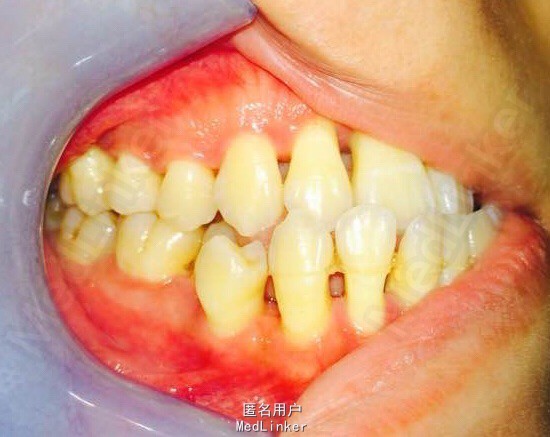

女,23岁,重度侵袭性牙周病,有家族遗传性

讨论: 牙周治疗处于维护稳定阶段,下合2—2牙槽骨吸收至根尖1/3水平,是否适合正畸? 下合前牙的保留问题?